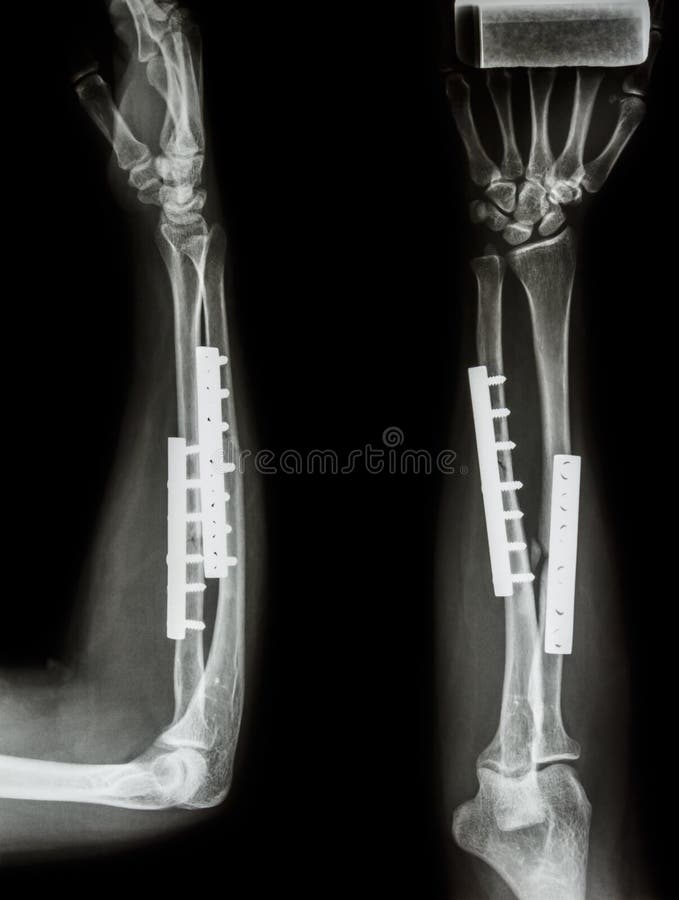

Медицинские снимки: Пластина в левом предплечье